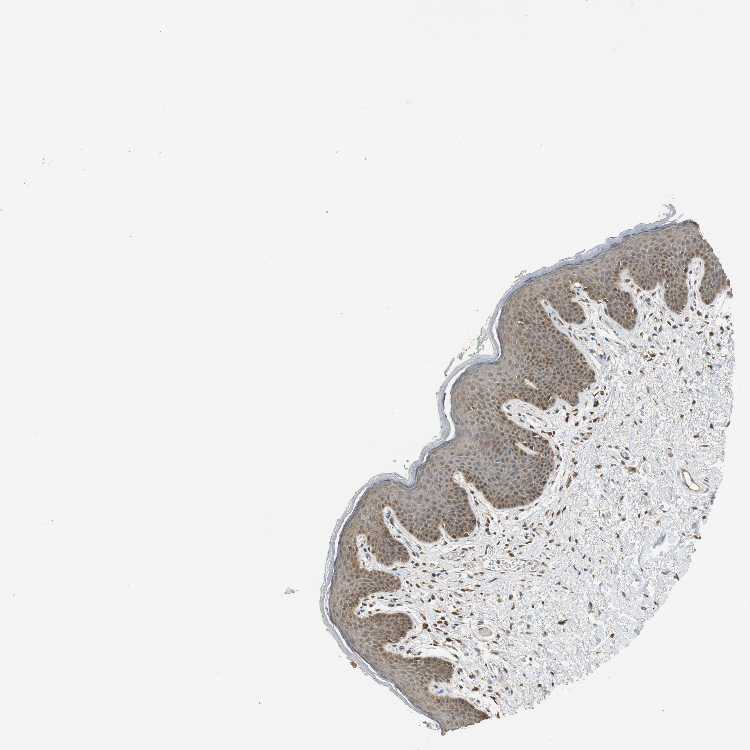

SKIN 1 - Antibody stainingi

Antibody staining in the annotated cell types in the current human tissue is reported as not detected, low, medium, or high, based on conventional immunohistochemistry profiling in selected tissues. This score is based on the combination of the staining intensity and fraction of stained cells.

Each image is clickable and will lead to virtual microscopy that enables deeper exploration of all samples and also displays staining intensity scores, fraction scores and subcellular localization as well as patient and tissue information for each sample.

Antibody HPA006431Antibody CAB013481

Langerhans -Medium

Cells in basal layer Medium-

Cells in corneal layer Not detected-

Cells in granular layer Low-

Cells in spinous layer Medium-

Eccrine glands Medium-

Endothelial cells Medium-

Extracellular matrix Not detected-

Fibroblasts -Medium

Fibrohistiocytic cells Medium-

Keratinocytes -Medium

Langerhans cells Medium-

Lymphocytes Medium-

Melanocytes MediumMedium

Vascular mural cells Low-